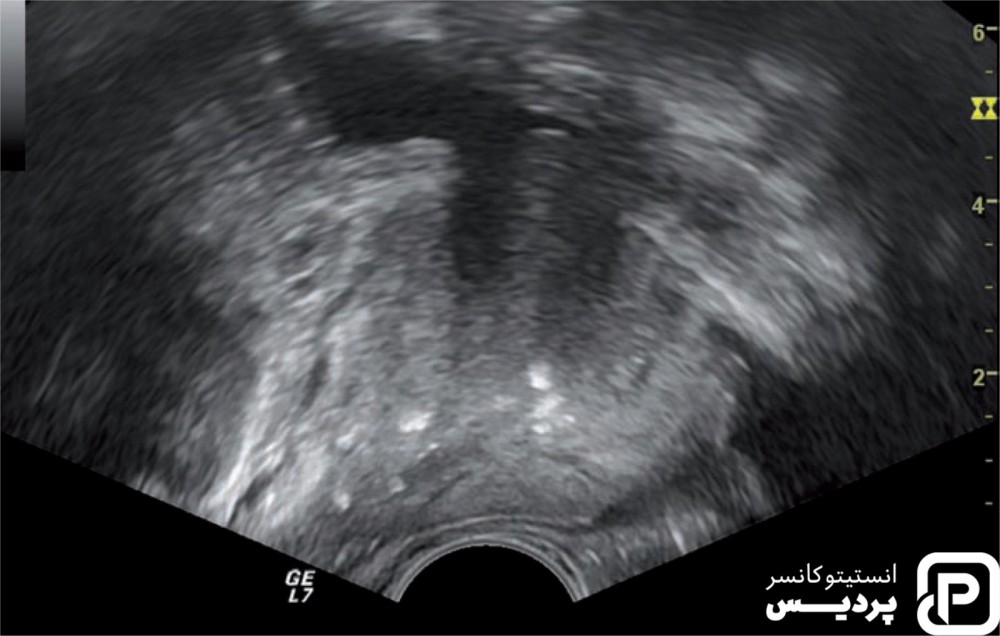

سونوگرافی ترشحی (TRUS)

برای این آزمایش کاوشگر کوچکی روغن کاری شده و از طریق مقعد وارد روده فرد می گردد. این کاوشگر امواج صوتی را به غده پروستات وارد و پژواک ایجاد می کند. این وسیله پژواک را جمع کرده و یک کامپیوتر آن ها را به تصویر سیاه و سفید از غده پروستات تبدیل می کند. این روش کمتر از ۱۰ دقیقه انجام شده و در مطب و به صورت سرپایی انجام می شود. این سونوگرافی معمولاً دردناک نمی باشد.

TRUS در موقعیت های مختلف مورد استفاده قرار می گیرد:

- برای جستجوی مناطق مشکوک در پروستات. مردانی که نتیجه آزمایش DRE و PSA آن ها غیر طبیعی بوده است.

- طی بیوپسی و نمونه برداری از پروستات برای هدایت سوزن به قسمت صحیح غده پروستات انجام می شود.

- برای اندازه گیری غده پروستات و به تعیین تراکم PSA کمک می کند.

در بعضی از روش های درمانی مانند براکی تراپی یا کرایوتراپی به عنوان راهنما مورد استفاده قرار می گیرد.